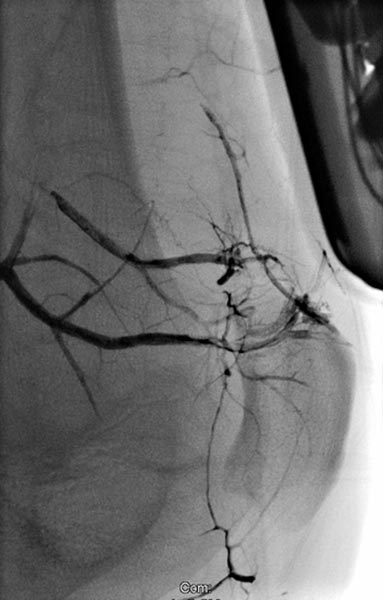

Digital subtraction angiography, with the catheter in the left superior gluteal artery, reveals multiple, barely identifiable small arteriovenous fistulas typical of the diffuse arteriovenous malformations seen in Parkes-Weber syndrome.

Superselective digital subtraction angiography via a microcatheter in the superior gluteal artery in a distal branch. The nidus of the fine fistulous arteriovenous malformation shows such fine shunts that they can hardly be resolved anatomically on angiography.